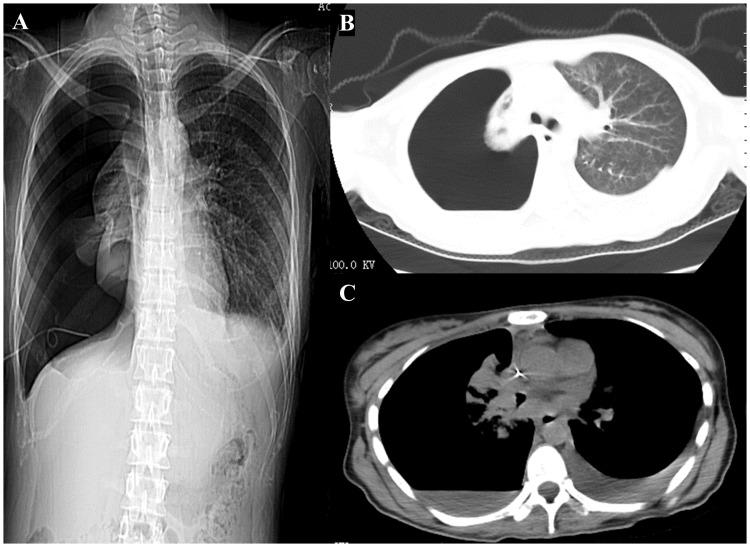

Nuclear protein of the testis (NUT) midline carcinoma (NMC) is a rare tumor, with particularly low incidence in the lungs, and a correspondingly poor prognosis. To determine the clinicopathological characteristics, outcomes, and prognostic factors of primary pulmonary NMC, a case was reported and a systematic review was performed. Twenty-nine records, including ours, involving 62 cases, were finally included. The median age at diagnosis was 29.5 years. At presentation, the most common symptoms at presentation were cough (47.50%) and chest/back pain (37.50%). In terms of diagnosis, 32.14% of NMC cases were identified through immunohistochemistry (IHC); However, a greater number of cases may be misdiagnosed initially, and ultimately, the diagnosis of NMC was confirmed through a combination of IHC and fluorescence hybridization (FISH). Despite the clinical application of various chemotherapy-based treatments, the actual effectiveness remains unsatisfactory. Furthermore, Cox regression analysis of multiple factors identified male gender and concurrent presence of pleural effusion as indicators of shorter survival time in patients. These results emphasize the importance of increased diagnostic awareness among clinical and pathology practitioners concerning NMC. While there is currently no established standard for treating NMC, a treatment approach combining multiple methods shows promise for future research. Concurrently, clinical and foundational investigations addressing variables such as gender and the presence of pleural effusion may yield valuable insights into the diagnosis and treatment of NMC.